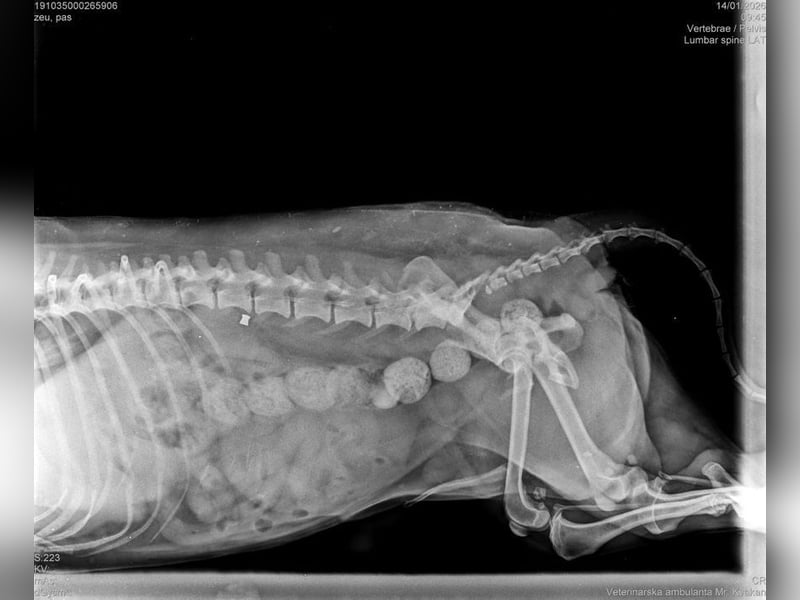

Die medizinische Untersuchung ergab, dass außer einem Schrecken, keine Verletzungen festzustellen waren. Auch die Röntgenaufnahmen bestätigten diese Diagnose.